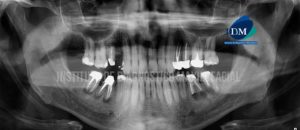

Paciente pediátrico de sexo masculino acude al Instituto de Diagnóstico Maxilofacial para evaluación imagenológica. En la radiografía panorámica observamos las estructuras óseas de características conservadas,